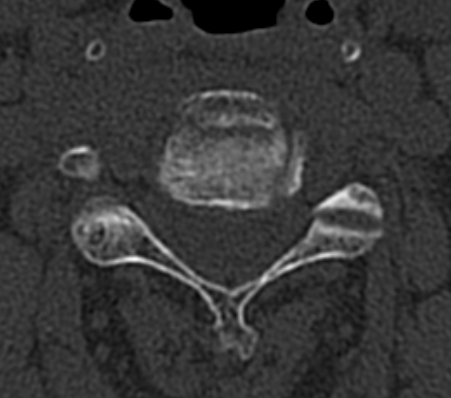

Xray / CT

Large antero-inferior body fragment / tear drop

- > 20 %

- stays attached to ALL

+/- posterior superior fragment retropulsed into canal